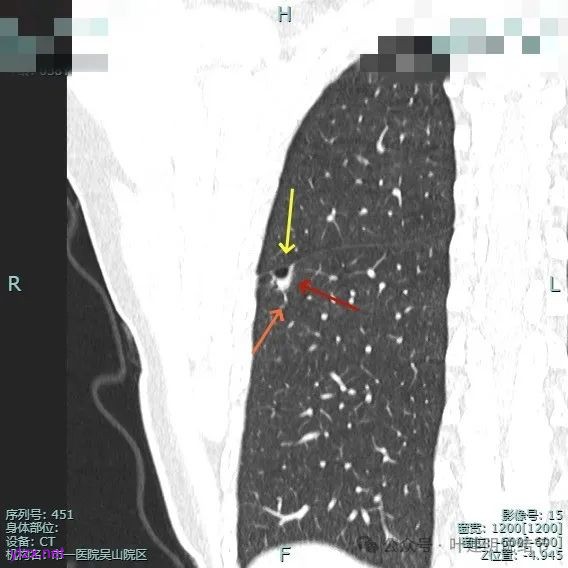

病灶部分囊壁是混合磨玻璃成分的,整体轮廓较清。

边缘区也有偏实性成分,磨玻璃成分也还是明显的,有微小血管进入。

靶重建的影像上看,病灶的囊壁明显厚薄不均,有小血管进入,一侧的边似就是斜裂的样子。

囊壁有磨玻璃成分,边缘毛糙,有少许偏实性成分,仍有磨玻璃成分。